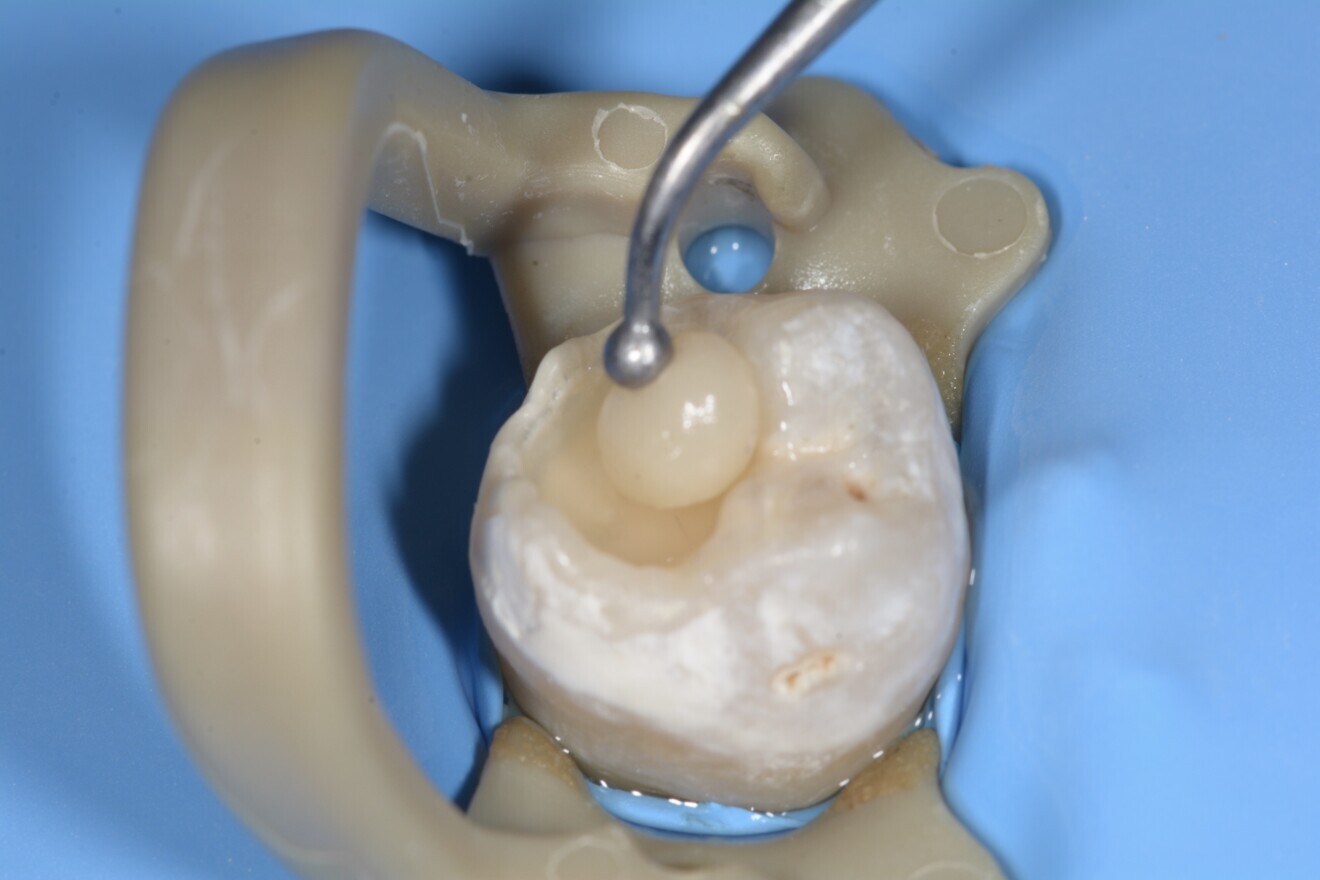

Fig. 1 : Situation préopératoire. (Photos : Joseph Sabbagh)

L’examen clinique a révélé plusieurs restaurations défectueuses et des caries occlusales sur les premières et deuxièmes molaires inférieures gauches (N° 36 et n° 37 [Fig. 1]).

Une anesthésie locale (Articaïne adrénalinée à 1 : 200.000), a été réalisée afin d’éviter tout inconfort au patient pendant la procédure de restauration. L’accès à la carie a été réalisée sous irrigation abondante et le tissu carieux excavé à l’aide d’une fraise en carbure de tungstène. Le champ de travail a été isolé à l’aide d’une digue pour éviter toute contamination par les fluides gingivaux (Fig. 2).